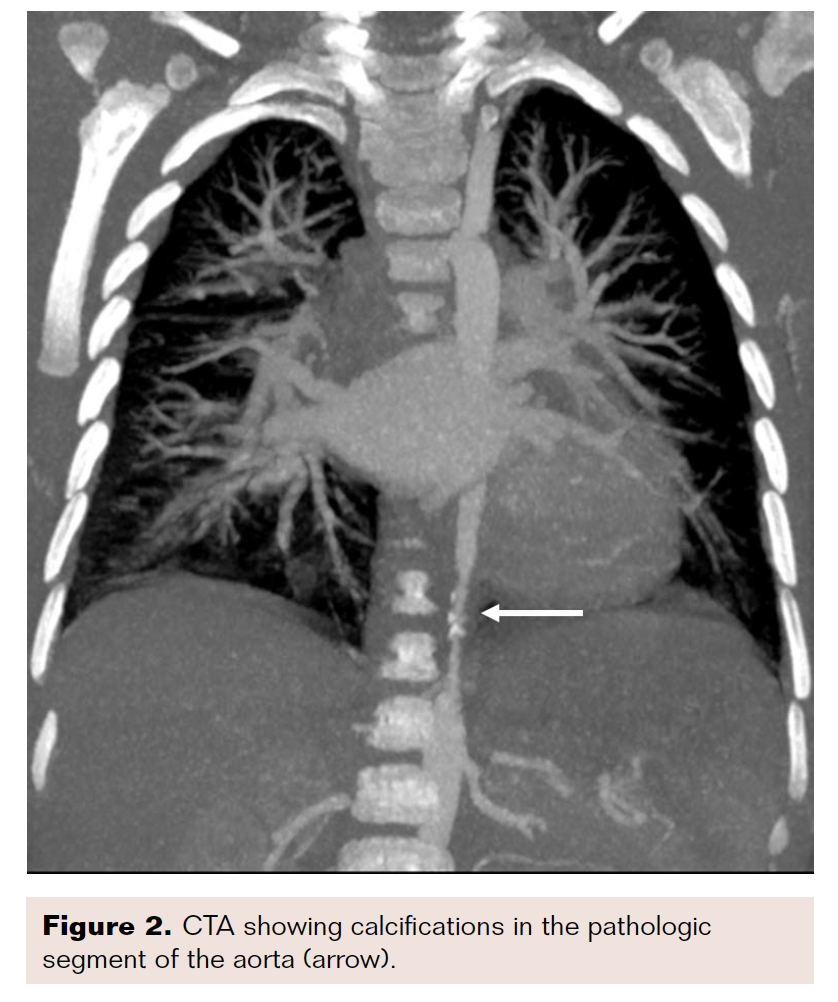

Computed tomography angiography (CTA) confirmed a diagnosis of a thoraco-abdominal aortic coarctation that was 38.6 mm in length, along with calcifications and obstruction of the celiac artery (CA), which was retrogradely perfused. The renal arteries (RA) and the superior mesenteric artery (SMA) were permeable (Figures 1-2).